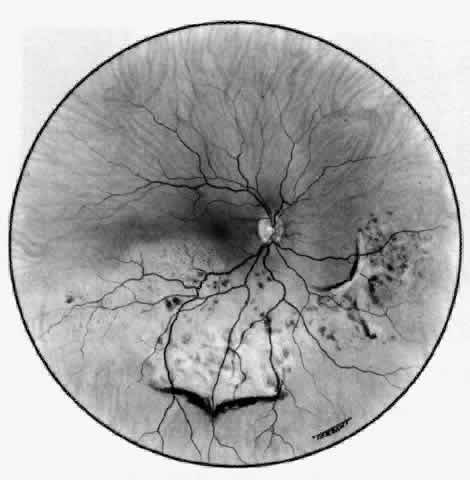

Posterior Scleritis

Because the posterior sclera is invisible, the diagnosis of posterior scleritis is made only if the anterior sclera is also involved or some other sign or symptom leads one to suspect it. Posterior scleritis is much more common than previously suspected, as recent clinical and pathologic studies have shown.19,28,29 There are two distinct forms of posterior scleritis. The first is usually associated with an anterior scleritis. This granulomatous disorder, like its anterior counterpart, can be diffuse, nodular, or necrotizing in character and is associated with the connective tissue diseases. The second form occurs in young patients of all races who are 9 to 40 years of age. It is always diffuse in character but is not associated with any systemic disorder. Both forms may cause uveitis if the inflammation affects the ciliary body, and in both forms the patient may develop exudative retinal detachments, choroidal folds, and swelling of the disc (Figs. 51 and 52). The granulomatous type may also involve the structures outside the globe, causing proptosis (Fig. 53), limitation of ocular muscle movement, and, uniquely, retraction of the lower lid on attempted elevation of the eye (Fig. 54). Diagnosis is with B-scan ultrasonography.

Fig. 52. Fundus appearance after resolution of exudative detachment in patient with severe posterior scleritis. Macula was affected and vision much impaired. (Watson PG: Management of scleritis. In: Recent Advances in Ophthalmology, Vol 5. London, Churchill-Livingstone, 1975)

TREATMENT